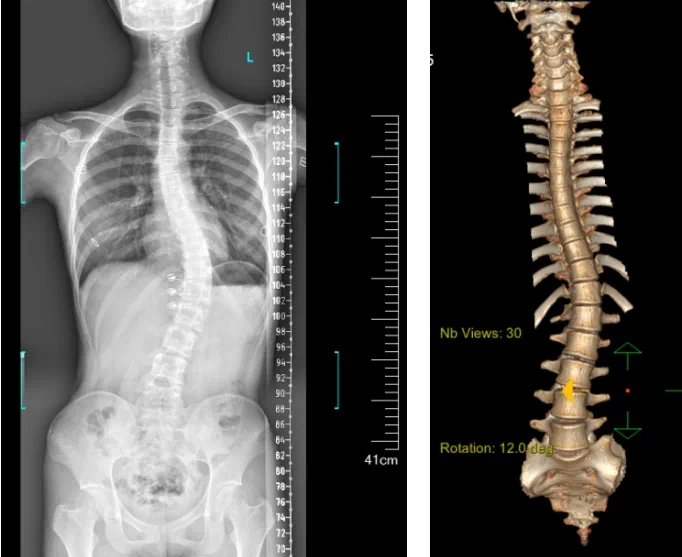

患者為一名16歲女孩,發(fā)現(xiàn)脊柱側(cè)彎1年,到南方醫(yī)院贛州醫(yī)院脊柱外科求診。經(jīng)查體,患者左右胸廓不對稱,雙肩等高,左肩胛骨隆起,背側(cè)呈“剃刀背”畸形,胸腰段棘突偏離正中線,胸腰段脊柱左側(cè)凸畸形;各棘突無壓痛及叩擊痛,右側(cè)腰部凹陷,胸腹及腰背部感覺正常。檢查發(fā)現(xiàn)患者特發(fā)性脊柱側(cè)彎,Lenke5C型,主胸彎51°?;颊呒凹覍賹ν庥^不滿意,為改善外觀及功能,要求手術(shù)矯形治療。

據(jù)悉脊柱側(cè)彎手術(shù)治療后可以保持軀干平衡,改善外觀并防止畸形進一步發(fā)展?;颊叩纳钯|(zhì)量得到提高,進而減少脊柱過度畸形可能帶來的疾病的發(fā)生率,外觀上的積極變化往往也能帶來患者心理與精神的積極變化。臨床上會綜合考慮患者的年齡、側(cè)彎程度、進展趨勢、骨質(zhì)條件、鄰近節(jié)段情況、手術(shù)節(jié)段等因素,合理采用個性化的手術(shù)方式進行治療。然而,由于脊柱神經(jīng)血管密布,手術(shù)操作相對復(fù)雜,手術(shù)難度高、風(fēng)險大,傳統(tǒng)脊柱側(cè)彎的手術(shù)方式往往有較高的神經(jīng)或脊髓損傷風(fēng)險。故此次科室決定開展機器人輔助導(dǎo)航下脊柱側(cè)彎矯形、植骨融合內(nèi)固定手術(shù)。術(shù)前,醫(yī)生團隊在機器人多維度圖像融合智能手術(shù)規(guī)劃功能的輔助下,預(yù)先規(guī)劃了理想的置釘路徑。術(shù)中,天璣骨科手術(shù)機器人準(zhǔn)確遵循術(shù)前規(guī)劃,根據(jù)配準(zhǔn)結(jié)果,實時定位并準(zhǔn)確執(zhí)行置釘操作,所有導(dǎo)針均用電鉆置入,一次性成功,協(xié)助醫(yī)生順利完成手術(shù)。最終,在麻醉科、手術(shù)室密切配合下,歷時3小時成功完成側(cè)彎矯形術(shù),出血量僅500ml。術(shù)后,患者恢復(fù)良好,大小便及下肢神經(jīng)運動感覺正常。

圖為置釘后